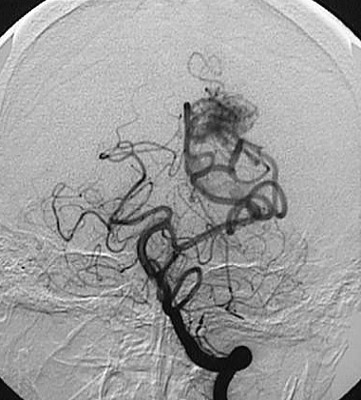

Cerebral angiography is an excellent method for demonstrating a

vascular malformation

, here a lesion in the left occipital lobe in coronal view. These lesions are often amenable to resection.